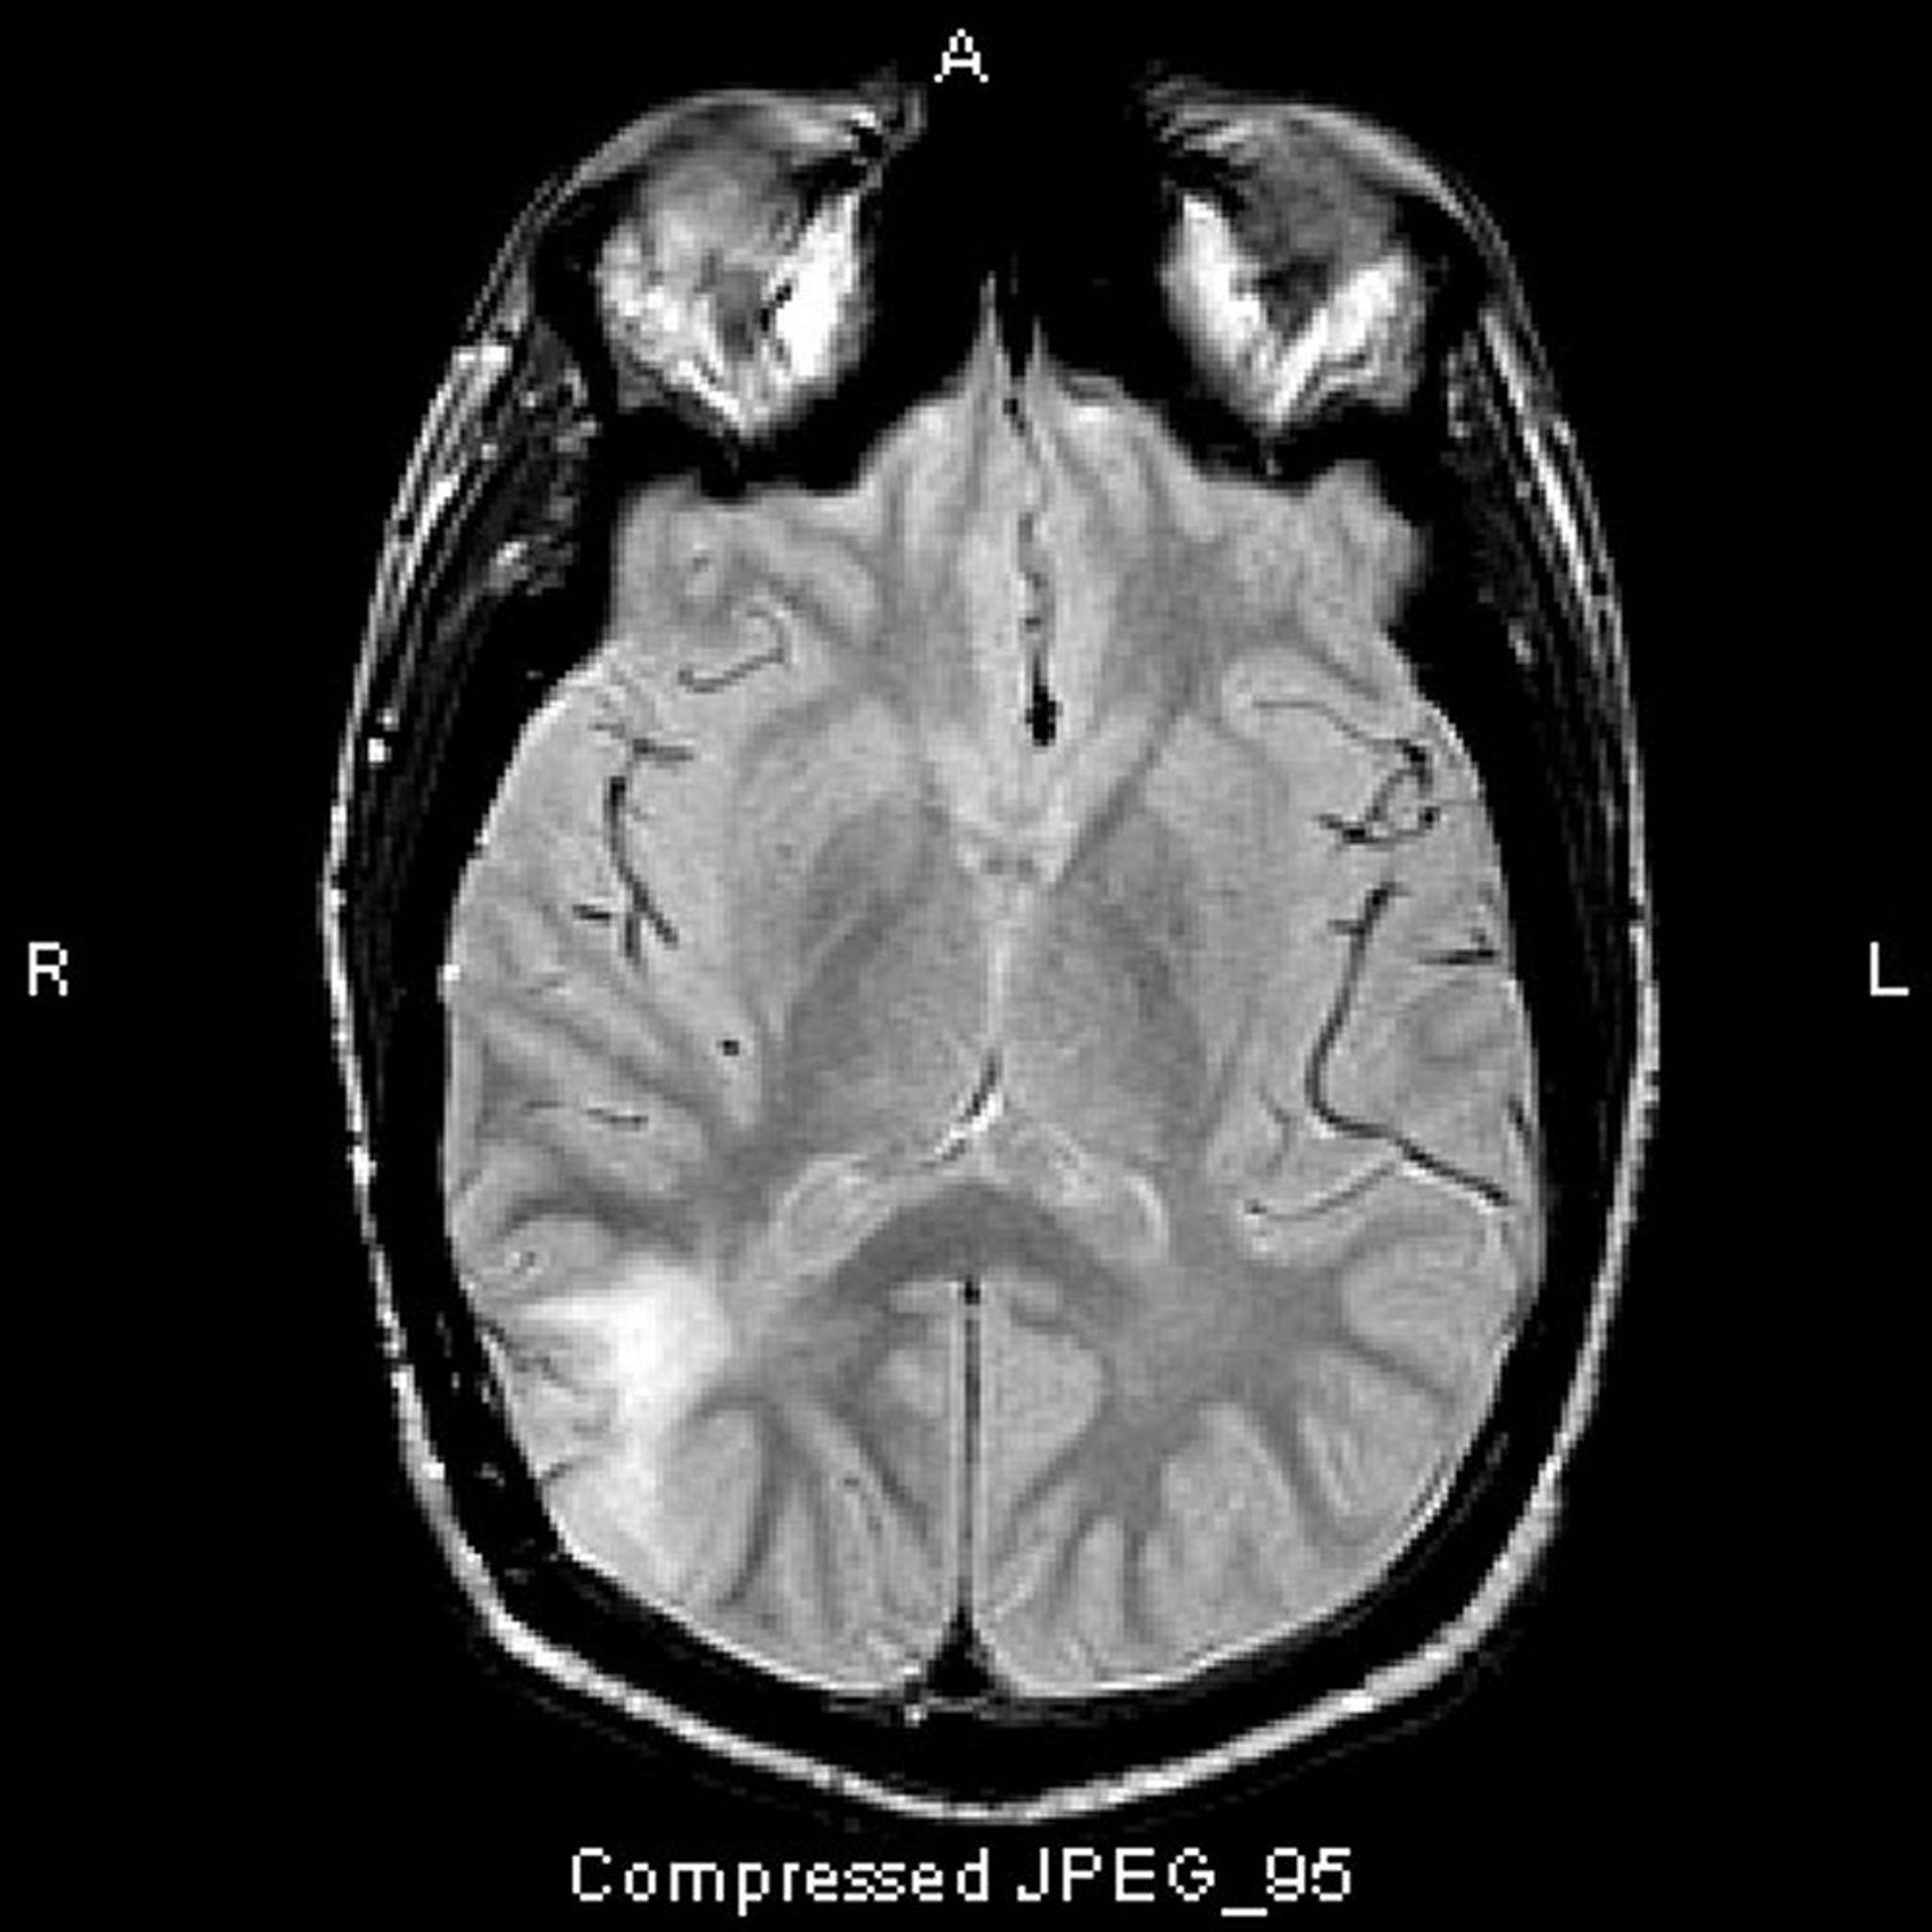

Hình chụp MRI T2-FLAIR này cho thấy tín hiệu màu trắng ở thùy thái dương sau. Tín hiệu không được tăng cường bởi chất tương phản. Đó là u sao bào giảm biệt hóa (độ III).

Hình ảnh do bác sĩ William R. Shapiro cung cấp